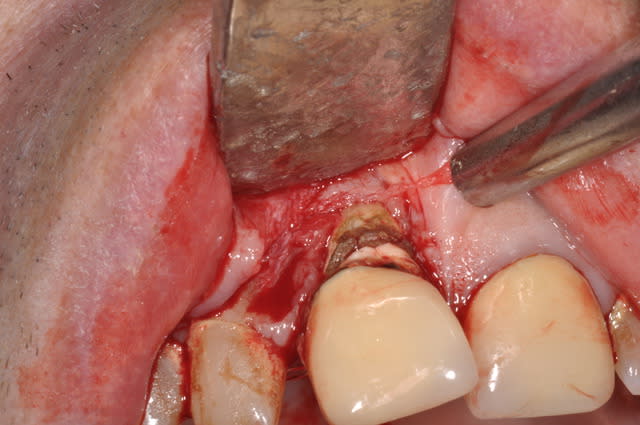

Je reviens sur ce cas, il va falloir que je lui fasse un plan de traitement correct.

Autre piste : ext des 4 incisives et bridge sur implants 12 22. ttt ortho -chir...

quelques nouvelles photos :